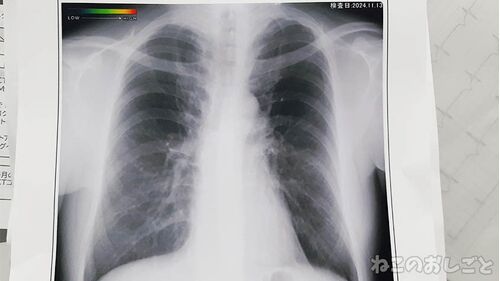

【謎の咳】治療を2ヶ月続けても咳が止まらない! 再びエコー&レントゲン撮影した結果は?

咳辛い 猫月さん持病みたいな感じて定期的に 咳が止まらなくなる病があるんだけど 大体1ヶ月程度逆流性食道炎のお薬を 飲むと治るんだよね。 なんか咳の原因は食道炎の刺激による もんだって事になってるのよ。 そんなんで1回咳が出るとその刺激で 再び咳が…